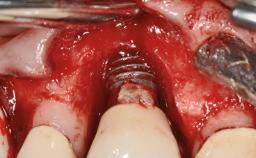

Oral Lichen Planus Associated with the Peri-implant Mucosa

This case describes the ongoing management of a 64-year-old healthy, non-smoking female patient with erosive oral lichen planus (OLP) affecting the gingivae and the buccal and lingual mucosa. The peri-implant mucosa was also affected subsequent to implant placement. The patient had osseointegrated implants (four in the maxilla, four in the mandible) placed following extraction of hopeless teeth and a healing period. The patient had a history of OLP prior to implant placement and had been referred to an oral-medicine specialist for definitive diagnosis and treatment. She exhibited generalized oral mucosal involvement. Following a clinical assessment, biopsy, and blood tests, she was treated with topical corticosteroids. Systemic prednisolone was reserved for severe flare-ups. Amphotericin lozenges were used in combination with corticosteroid treatment to prevent the development of oral candidiasis.

# of Implants 8